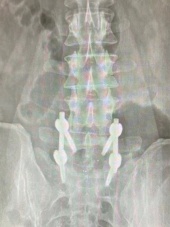

手术过程很顺利,精准定位之后,谢宁主任医师在病人腰部开了4个15mm的钥匙孔切口,手术操作全程在脊柱内镜下完成,放大20倍的影像把神经、血管看得一清二楚,手术工具都是毫米级的,对正常的肌肉几乎没有影响,精准的去除很少量骨质,摘除巨大脱出的腰椎间盘组织,出血几乎忽略不计。手术结束不放引流管,术后第2天下地,全程住院5天。术后3个月复查时,拍片显示植骨已经融合;小张健步如飞,又驰骋在篮球场上,他非常满意。

仅有4个15mm长的“钥匙孔”切口

术后3个月复查的X线片